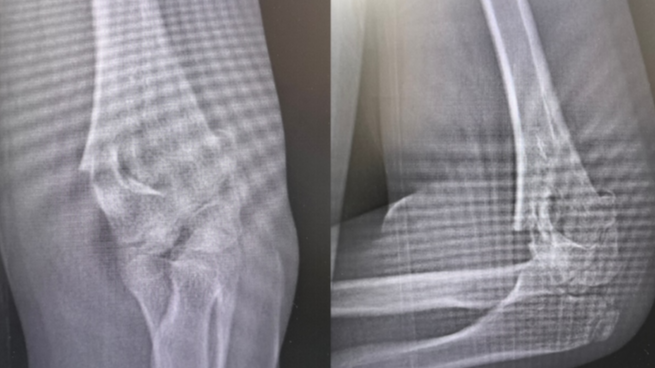

近日,广州医科大学附属第二医院创伤骨科(骨科三区)收治了一名因为摔伤的小患者俊俊(化名)。11岁的俊俊摔伤后左侧肘部逐渐肿痛,左胳膊无法活动,家长随即带他到医院就诊,医生结合患儿入院情况、体征、X线检查等,明确诊断为左肱骨髁上骨折并肘关节周围软组织肿胀。接诊医生立即给予患者左上肢石膏固定制动,并收住院治疗。

急诊X线提示:左肱骨髁上骨折(受访者供图)